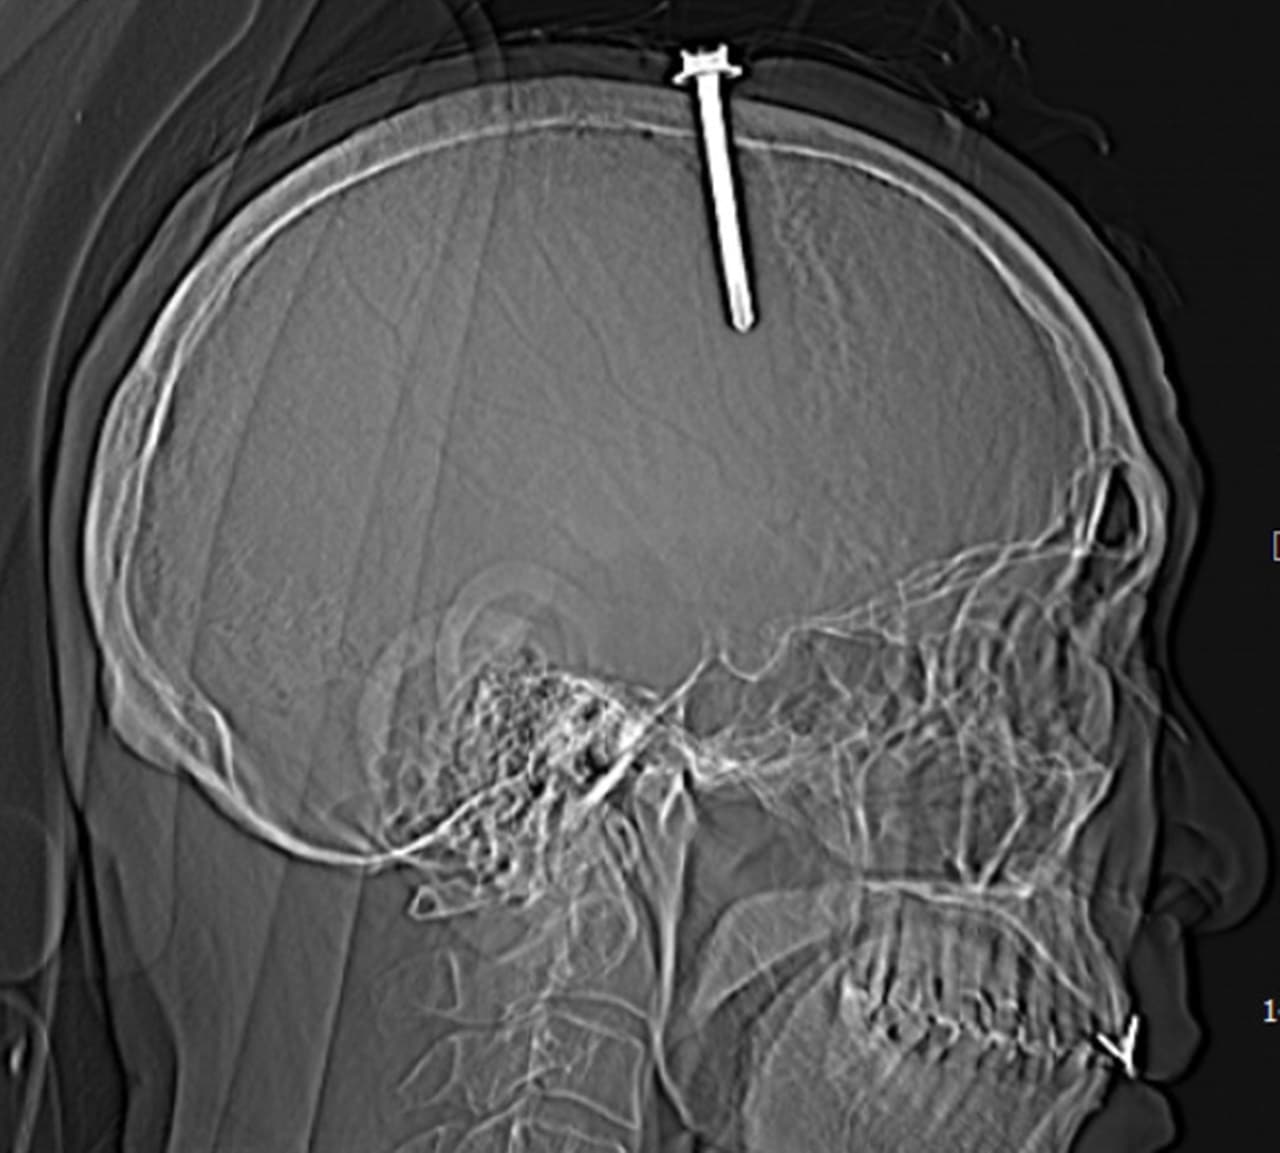

Qua thăm khám lâm sàng và chụp cắt lớp vi tính sọ não, bệnh nhân được xác định có vết thương sọ não, vết thương xoang tĩnh mạch dọc trên do dị vật kim loại cắm vào vùng đỉnh bên trái, cạnh xoang tĩnh mạch dọc trên. Dị vật có đường kính 0,5 cm, chiều dài 5,1cm.

Các bác sĩ đã khoan sọ xung quanh đinh, mở volet xương sọ lấy đinh ra ngoài, mở màng cứng kiểm tra phát hiện xoang tĩnh mạch dọc trên bị rách, đinh đâm sâu vào trong nhu mô não thùy đỉnh, máu chảy nhiều. Các bác sĩ tiến hành vá kín thành bên xoang tĩnh mạch dọc trên, cầm máu nhu mô não, vá kín màng cứng.